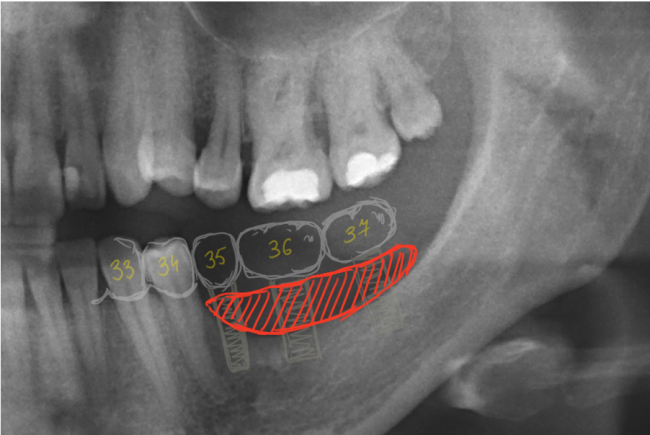

Sketch94233528

Их несколько, они обозначены на снимке.

1. Значительная атрофия костной ткани, особенно по высоте. Решается: остеопластической операцией.

2. Дефицит слизистой оболочки почти всегда сопровождает атрофию кости. Следовательно, после имплантации (либо до нее) нам потребуется пластика десны. Я предпочитаю это делать на этапе установки формирователей десны.

3. Зубоальвеолярное удлинение в области зубов-антагонистов. Решается: ортодонтическим лечением.

Sketch94232818

По данной схеме уже видно, какого объема костной ткани нам не хватает. В дополнение к снимкам, в клинике мы часто делаем диагностические модели, на которых восстанавливаем зубы и отсутствующую костную ткань с помощью воска — это т. н. WaxUp. Так мы моделируем и можем увидеть конечный результат нашей работы и планировать операцию. К сожалению, WaxUp показать не могу (поленился сфотографировать, лошара ;-)).

Sketch9423300

Это вполне осуществимо с помощью операции остеопластики, «наращивания костной ткани».